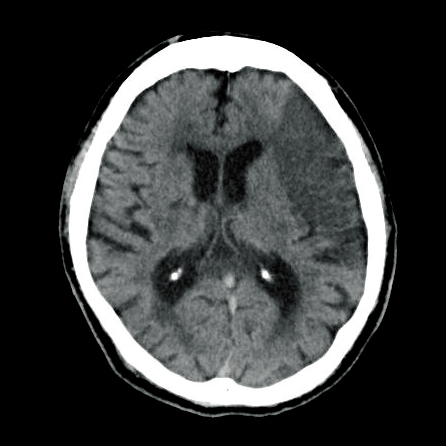

CTでおおまかな異変をつかむ

通常、緊急時の画像撮影はCT(コンピュータ断層撮影)が選択されます。

なぜ緊急時にCTを撮影するのかというと、CTでは検査前に「妊娠の有無」以外に確認が必要な項目がなく、迅速に検査を受けることができ、検査自体も数分で終了するためです。

また、脳卒中や頭部外傷など、緊急に対処しなければいけない疾患の評価や頭蓋内圧亢進の有無なども把握できます。さらに、画像所見と全身状態から、外科的治療、保存的治療の判断、原因検索のためにほかにどの検査が必要か、悪化させないための血圧管理や鎮静の必要性などの判断にもつながります。

CTで医師が見ているポイント

画像診断の重要なポイントとしては、疾患の特定だけでなく、どこに病巣があるか、その程度に関しても確認を行います。

例えば、患者さんに突然の半身の運動麻痺が出現した場合や頭部外傷後意識障害を伴った場合、画像所見で「高吸収域(脳出血やくも膜下出血などの出血性病変の有無)」、もしくは「低吸収域(脳梗塞などの虚血性病変の有無)」があるかどうかによって疾患を特定し、病変の範囲や頭蓋内圧亢進を起こしていないかも判断します。

さらに麻痺の症状と画像所見が一致しているか、他の随伴症状がないかも確認します。